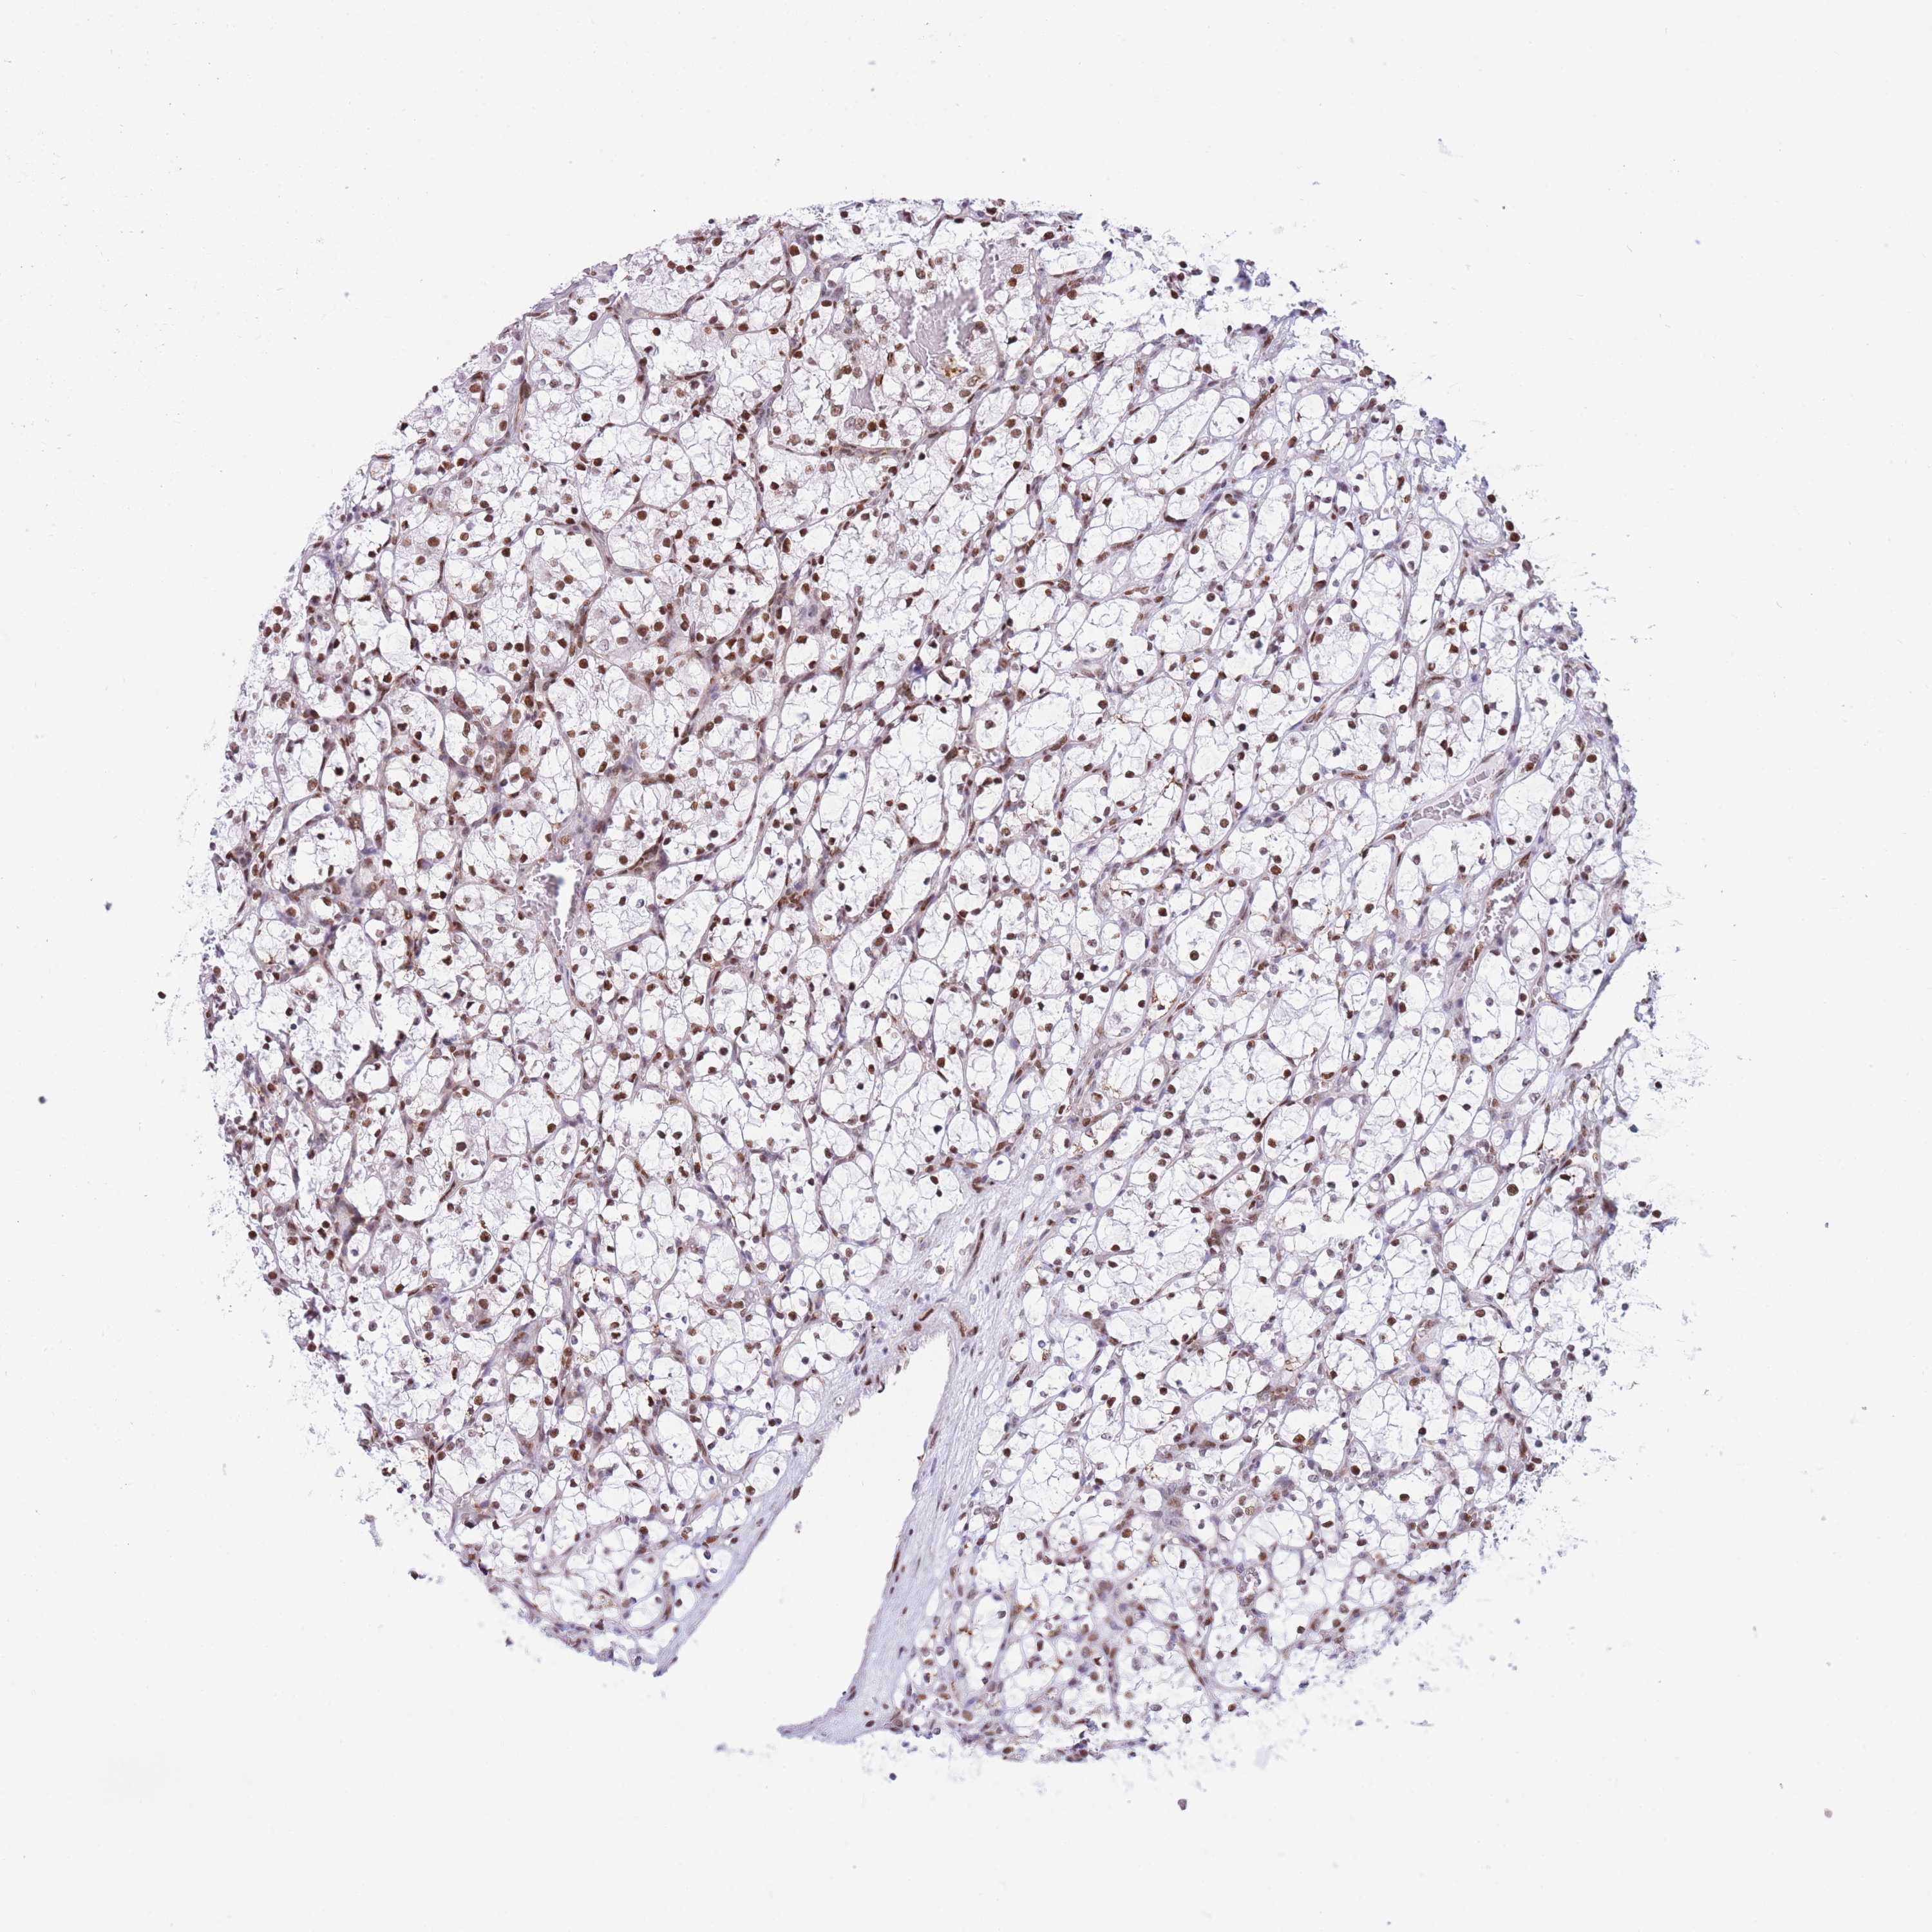

KIDNEY RENAL CLEAR CELL CARCINOMA (VALIDATION) - Interactive survival scatter ploti

The Survival Scatter plot shows the clinical status (i.e. dead or alive) for all individuals in the patient cohort, based on the same data that underlies the corresponding Kaplan-Meier plots. Patients that are alive at last time for follow-up are shown in blue and patients who have died during the study are shown in red.

The x-axis shows the expression levels (FPKM) of the investigated gene in the tumor tissue at the time of diagnosis. The y-axis shows the follow-up time after diagnosis (years). Both axes are complimented with kernel density curves demonstrating the data density over the axes. The top density plot shows the expression levels (FPKM) distribution among dead (red) and alive patients (blue). The right density plot shows the data density of the survived years of dead patients with high and low expression levels respectively, stratified using the cutoff indicated by the vertical dashed line through the Survival Scatter plot. This cutoff is automatically defined based on the FPKM cutoff that minimizes the p-score. The cutoff can be changed by dragging the vertical line or by entering a cutoff value in the square labeled "Current cut-off".

Under the Survival Scatter plot the p-score landscape (black curve; left axis) is shown together with dead median separation (red curve; right axis). Dead median separation is the difference in median mRNA expression between patients who have died with high and low expression, respectively. It is calculated as follows: median FPKM expression of dead patients with high expression - median FPKM expression of dead patients with low expression. This is intended to aid the user in visually exploring custom cutoffs and the associated p-scores and dead median separation.

Individual patient data is displayed and can be filtered by clicking on one or more of the category buttons on the top of the page. Categories describing expression level and patient information include: high, low, alive, dead, female, male and tumor stages. The scale of the x-axis can be toggled between linear and log-scale by clicking on the "x log" button. Mouse-over function shows TCGA ID, patient information and mRNA expression (FPKM) for each patient.

& Survival analysisi

Kaplan-Meier plots summarize results from analysis of correlation between mRNA expression level and patient survival. Patients were divided based on level of expression into one of the two groups "low" (under cut off) or "high" (over cut off). X-axis shows time for survival (years) and y-axis shows the probability of survival, where 1.0 corresponds to 100 percent.

DNAJC3 is not prognostic in Kidney Renal Clear Cell Carcinoma (validation)

: 42.28

Average pTPM 43.0

Number of samples 100